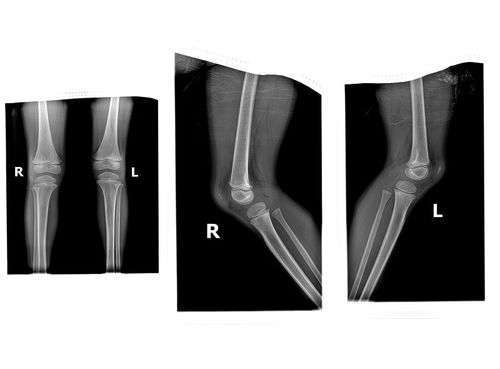

重复髌骨1例